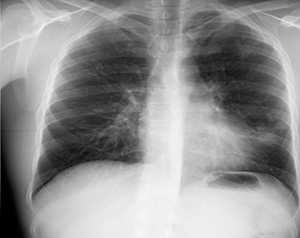

Данное Z3≤1,07, прогнозируем длительность применения ИП в течение 3-х месяцев. ИП поддерживали на протяжении 3-х месяцев. Каверна закрылась (см. рис. 4).